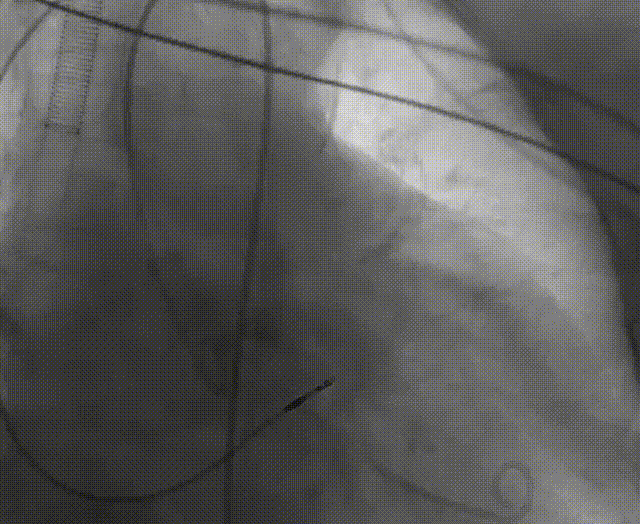

手术流程概括

22球囊扩张,无明显腰增,无造影剂泄露。

瓣膜初始零位释放,释放后位置尚可,决定完全释放。

瓣膜释放后有瓣周漏显示决定进行球囊后扩。

后扩后形态良好,瓣膜展开充分,轻微瓣周漏。